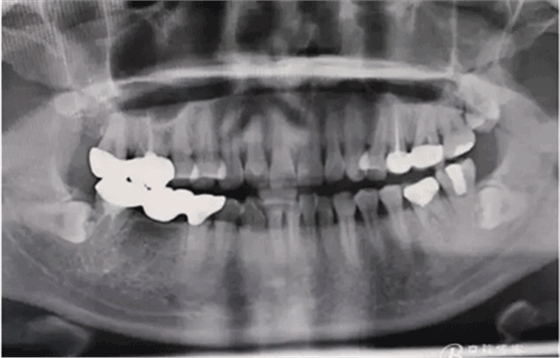

圖1.下頜47-45全瓷橋修復(fù),17、16全瓷連冠修復(fù)。48低位水平阻生。